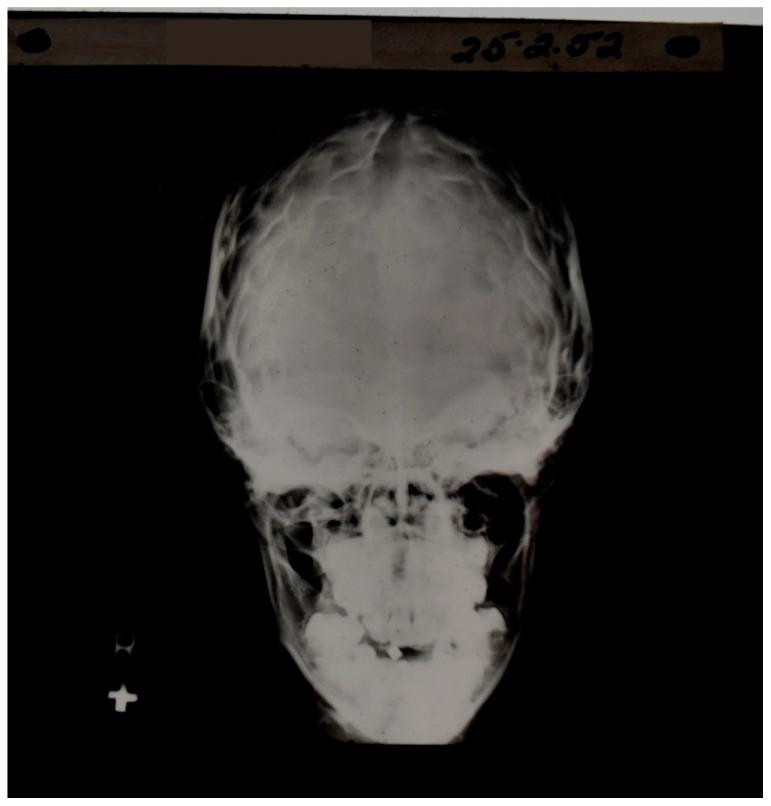

Ultra-high contrast (UHC) MRI describes forms of MRI in which little or no contrast is seen on conventional MRI images but very high contrast is seen with UHC techniques. One of these techniques uses the divided subtracted inversion recovery (dSIR) sequence, which, in modelling studies, can produce ten times the contrast of conventional inversion recovery (IR) sequences. When used in cases of mild traumatic brain injury (mTBI), the dSIR sequence frequently shows extensive abnormalities in white matter that appears normal when imaged with conventional T-fluid-attenuated IR (T-FLAIR) sequences. The changes are bilateral and symmetrical in white matter of the cerebral and cerebellar hemispheres. They partially spare the anterior and posterior central corpus callosum and peripheral white matter of the cerebral hemispheres and are described as the whiteout sign. In addition to mTBI, the whiteout sign has also been seen in methamphetamine use disorder and Grinker's myelinopathy (delayed post-hypoxic leukoencephalopathy) in the absence of abnormalities on T-FLAIR images, and is a central component of post-insult leukoencephalopathy syndromes. This paper describes the concept of ultra-high contrast MRI, the whiteout sign, the theory underlying the use of dSIR sequences and post-insult leukoencephalopathy syndromes.

超高对比(UHC)MRI 描述了这样一些 MRI 形式,在常规 MRI 图像上几乎没有或没有对比,但在 UHC 技术中可以看到非常高的对比。其中一种技术使用分裂相减反转恢复(dSIR)序列,在建模研究中,该序列可以产生比常规反转恢复(IR)序列高十倍的对比度。当用于轻度创伤性脑损伤(mTBI)时,dSIR 序列经常在白质中显示出广泛的异常,而在使用常规 T 液衰减反转恢复(T-FLAIR)序列成像时,白质看起来正常。这些变化在大脑和小脑半球的白质中是双侧对称的。它们部分保留了前中央和后中央胼胝体以及大脑半球的外周白质,被描述为“白化征”。除了 mTBI 之外,在没有 T-FLAIR 图像异常的情况下,该白化征也出现在苯丙胺使用障碍和 Grinker 髓鞘病(缺氧后迟发性白质脑病)中,是创伤后白质脑病综合征的一个核心组成部分。本文描述了超高对比 MRI、白化征、dSIR 序列使用的理论以及创伤后白质脑病综合征的概念。